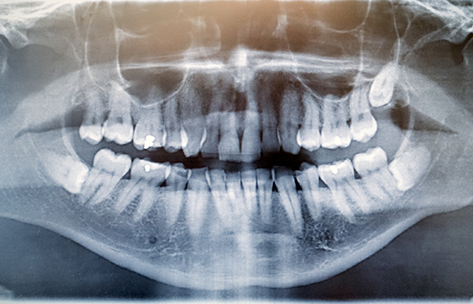

In almost all cases, wisdom teeth are completely formed at 18 years of age. It is therefore recommended that the removal take place between the ages of 14 to 18. But not all cases are the same, and through further analysis, the right time would be determined on a patient-to-patient basis. Often, a general or family dentist will be the first to discover an issue with the wisdom teeth - typically through X-rays during routine dental checkups. During the extraction, a patient will be numbed with a local anesthetic, and then their doctor will remove any gum or bone tissue that is still encapsulating the tooth before removing the tooth itself. The treatment site would then be closed using self-dissolving stitches. Oftentimes, our patients opt to have the procedure performed while asleep under IV anesthesia for comfort.